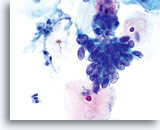

Er kan veelvuldig insnoeren worden waargenomen in zowel endocervicaal adenocarcinoom, als in endometriaal adenocarcinoom.

60x